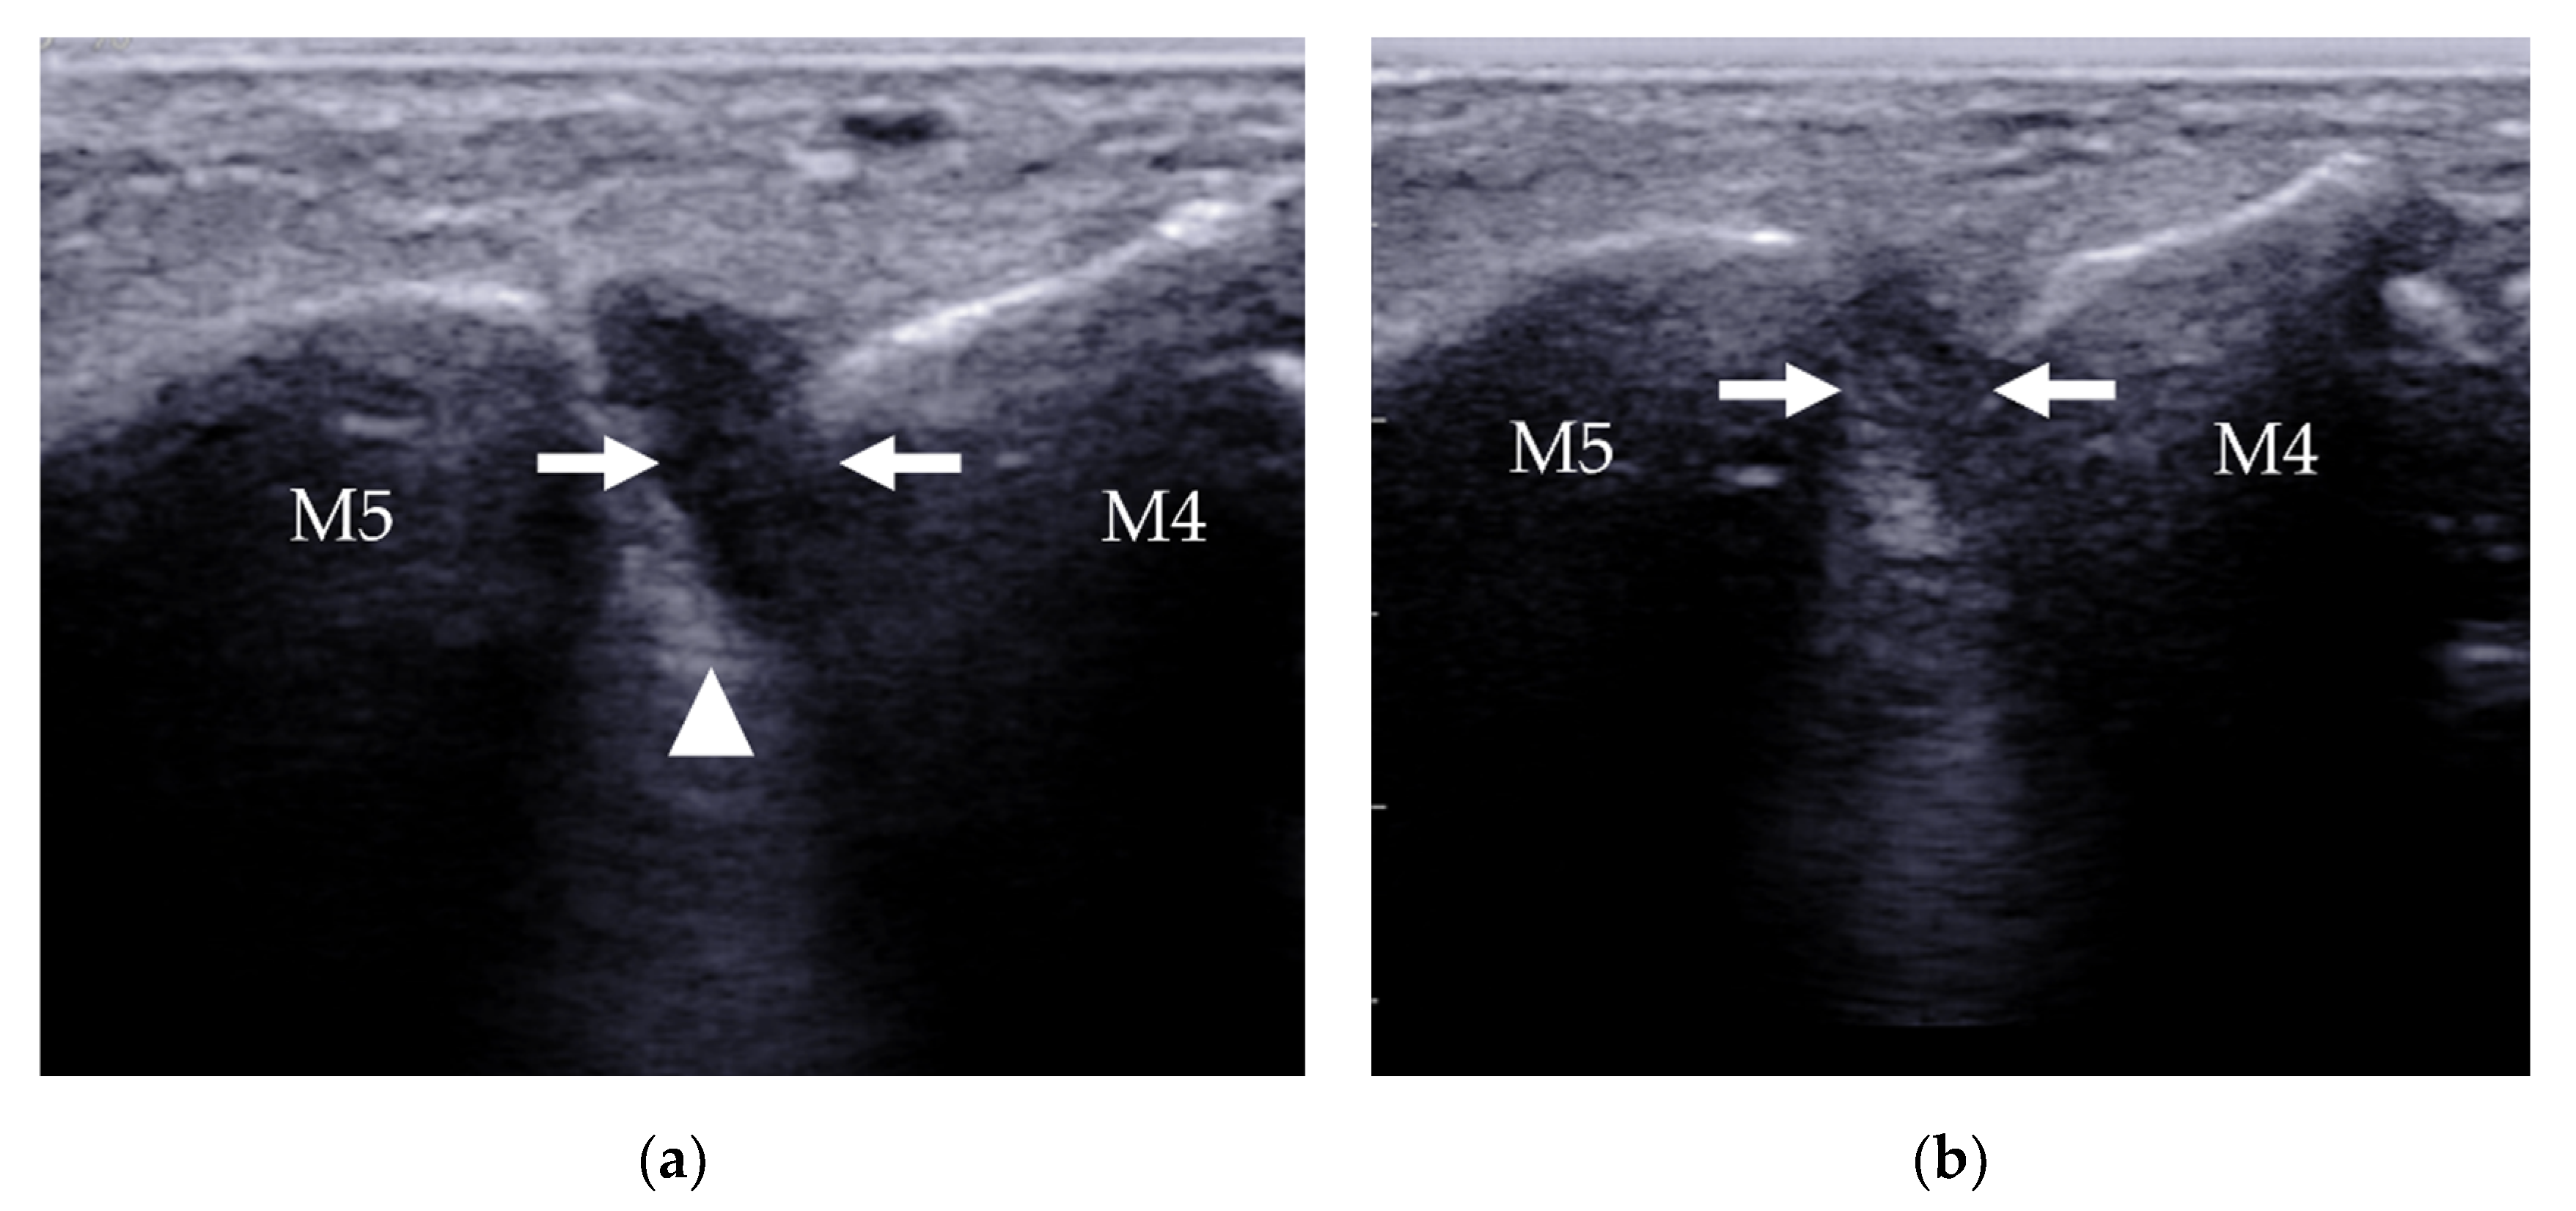

4.2.3. Intermetatarsal Bursitis

| Intermetatarsal bursitis | intermetatarsal spaces between 2nd and 3rd toes | hypoechoic mass with increased vascularity, compressible |